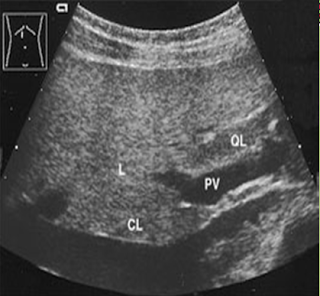

Explain the procedure of a liver exam.

Begin doing a full sweep through the liver. Starting sagittal,

slightly to the left of midline. Change to a transverse view and sweep

up and down the left lobe from a subcostal approach. Look in

transverse through the right lobe subcostally or

intercostally.

Look for:

- Parenchymal echogenicity

- Capsular contour (smooth, coarse, lobulated)

- Size

- Vascularity

- Fluid

- Masses

Start taking images.

Document the normal anatomy and

any pathology found, including measurements and vascularity if indicated.

What is the liver protocol?

Sagittal

Left lobe (wedge)

Left lobe W/ caudate

lobe

Left lobe W/ aorta

Right lobe W/ IVC

Right lobe W/

dome

Right lobe W/ Morrison’s pouch

Liver/kidney

comparison

Right lobe W/ gallbladder

Transverse

Left lobe W/ portal

vein

Left lobe W/ ligament teres

Right lobe W/ hepatic

veins, IVC

Right lobe W/ dome

Right lobe W/ portal

veins

Right lobe W/ kidney and gallbladder